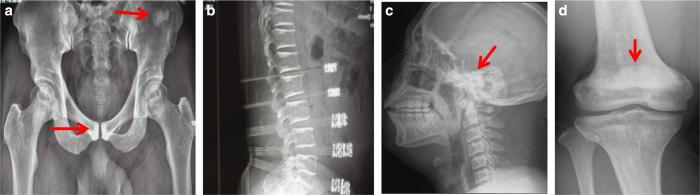

Type II autosomal dominant osteopetrosis (ADO2), which is the most common form of osteopetrosis, is caused by heterozygous mutations in the chloride channel 7 () gene. The osteopetrosis of ADO2 has been attributed to hypofunctional osteoclasts. The mechanism underlying the abnormality in osteoclast function remains largely unknown. This study was designed to investigate gene mutations and osteoclast function in a case that was clinically diagnosed as ADO2. Genomic DNA was extracted from blood samples of this patient, and the 25 exons of were amplified. Peripheral blood from the ADO2 subject and a healthy age- and sex-matched control was used to evaluate osteoclastogenesis, osteoclast morphology, and bone resorption. Analysis of DNA from the patient showed a germline heterozygous missense mutation, c.1856C>T (p.P619L), in exon 20 of . A similar homozygous mutation at this site was previously reported in a patient with autosomal recessive osteopetrosis. When cultured, the peripheral blood mononuclear cells (PBMCs) from the ADO2 patient spontaneously differentiated into mature osteoclasts . The ADO2 patient's PBMCs formed enhanced, but heterogeneous, osteoclasts in both the presence and absence of macrophage-colony stimulating factor, and nuclear factor-ĸB ligand. Bone resorption was reduced in the ADO2 patient's osteoclasts, which exhibited aberrant morphology and abnormal distribution of integrin aβ. Gene analysis found increased expression and reduced and expression in ADO2 cells. In conclusion, our data suggest that enhanced, heterogeneous osteoclast induction may be an intrinsic characteristic of ADO2.